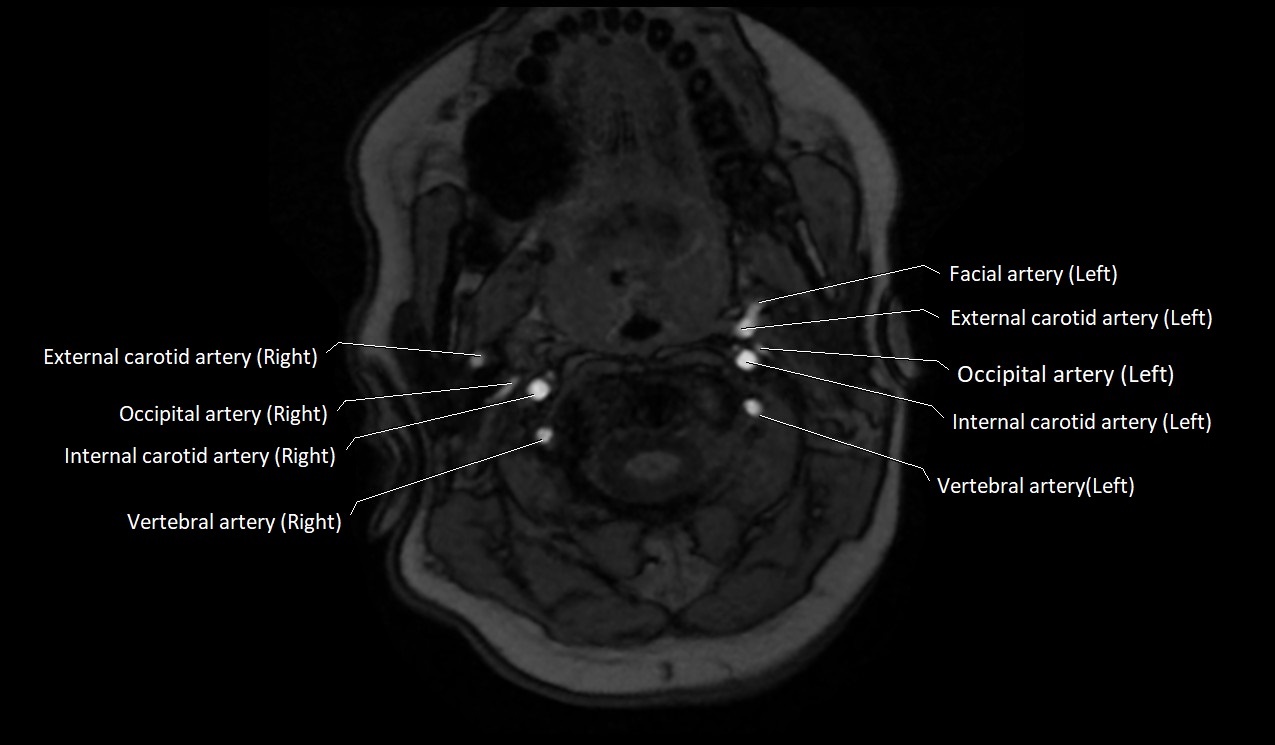

MRI Appearance:

• T1-Weighted Images:

• Appears as a tubular, hypointense (dark) structure relative to muscle

• May show flow void if the blood flow is fast

• T2-Weighted Images:

• Typically hypointense or isointense to muscle, but can be hyperintense if slow flow or stasis is present

MRI images

image